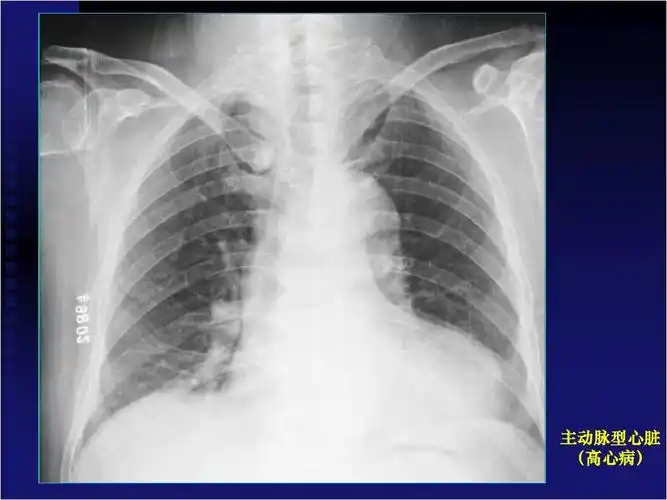

shs具有特征性的x线表现,心影小而狭长,各弧度平滑,心膈间隙较宽,长轴

阅读x线胸片,这是一个靴形心脏的胸片.